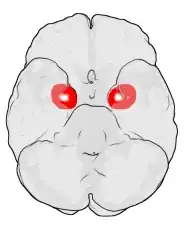

Amygdala

CG illustration of the amygdala's location

One of the main regions commonly associated with APD and antisocial behavior, and in particular with its remorselessness criterion, are the amygdala (Blair and Frith, 2000). However, while the amygdala's heavy involvement in emotional processing is well established (Kandel, 2013), and a veritable sea of studies support an emotional processing deficits and abnormalities in the amygdala for general antisocial behavior (e.g., Coccaro et al., 2006; Narayan et al., 2007; Veit et al., 2002) over different antisocial disorders, I couldn't find any direct investigations of amygdaloid activity in APD patients.